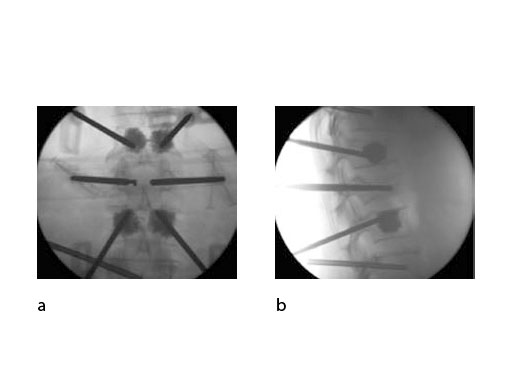

Both guide wire and trocar can be inserted through either a transpedicular (Fig 2a) or extrapedicular (Fig 2b) approach. The trocar allows access in a single step while the wire guide is first used to create a path for the access instruments.